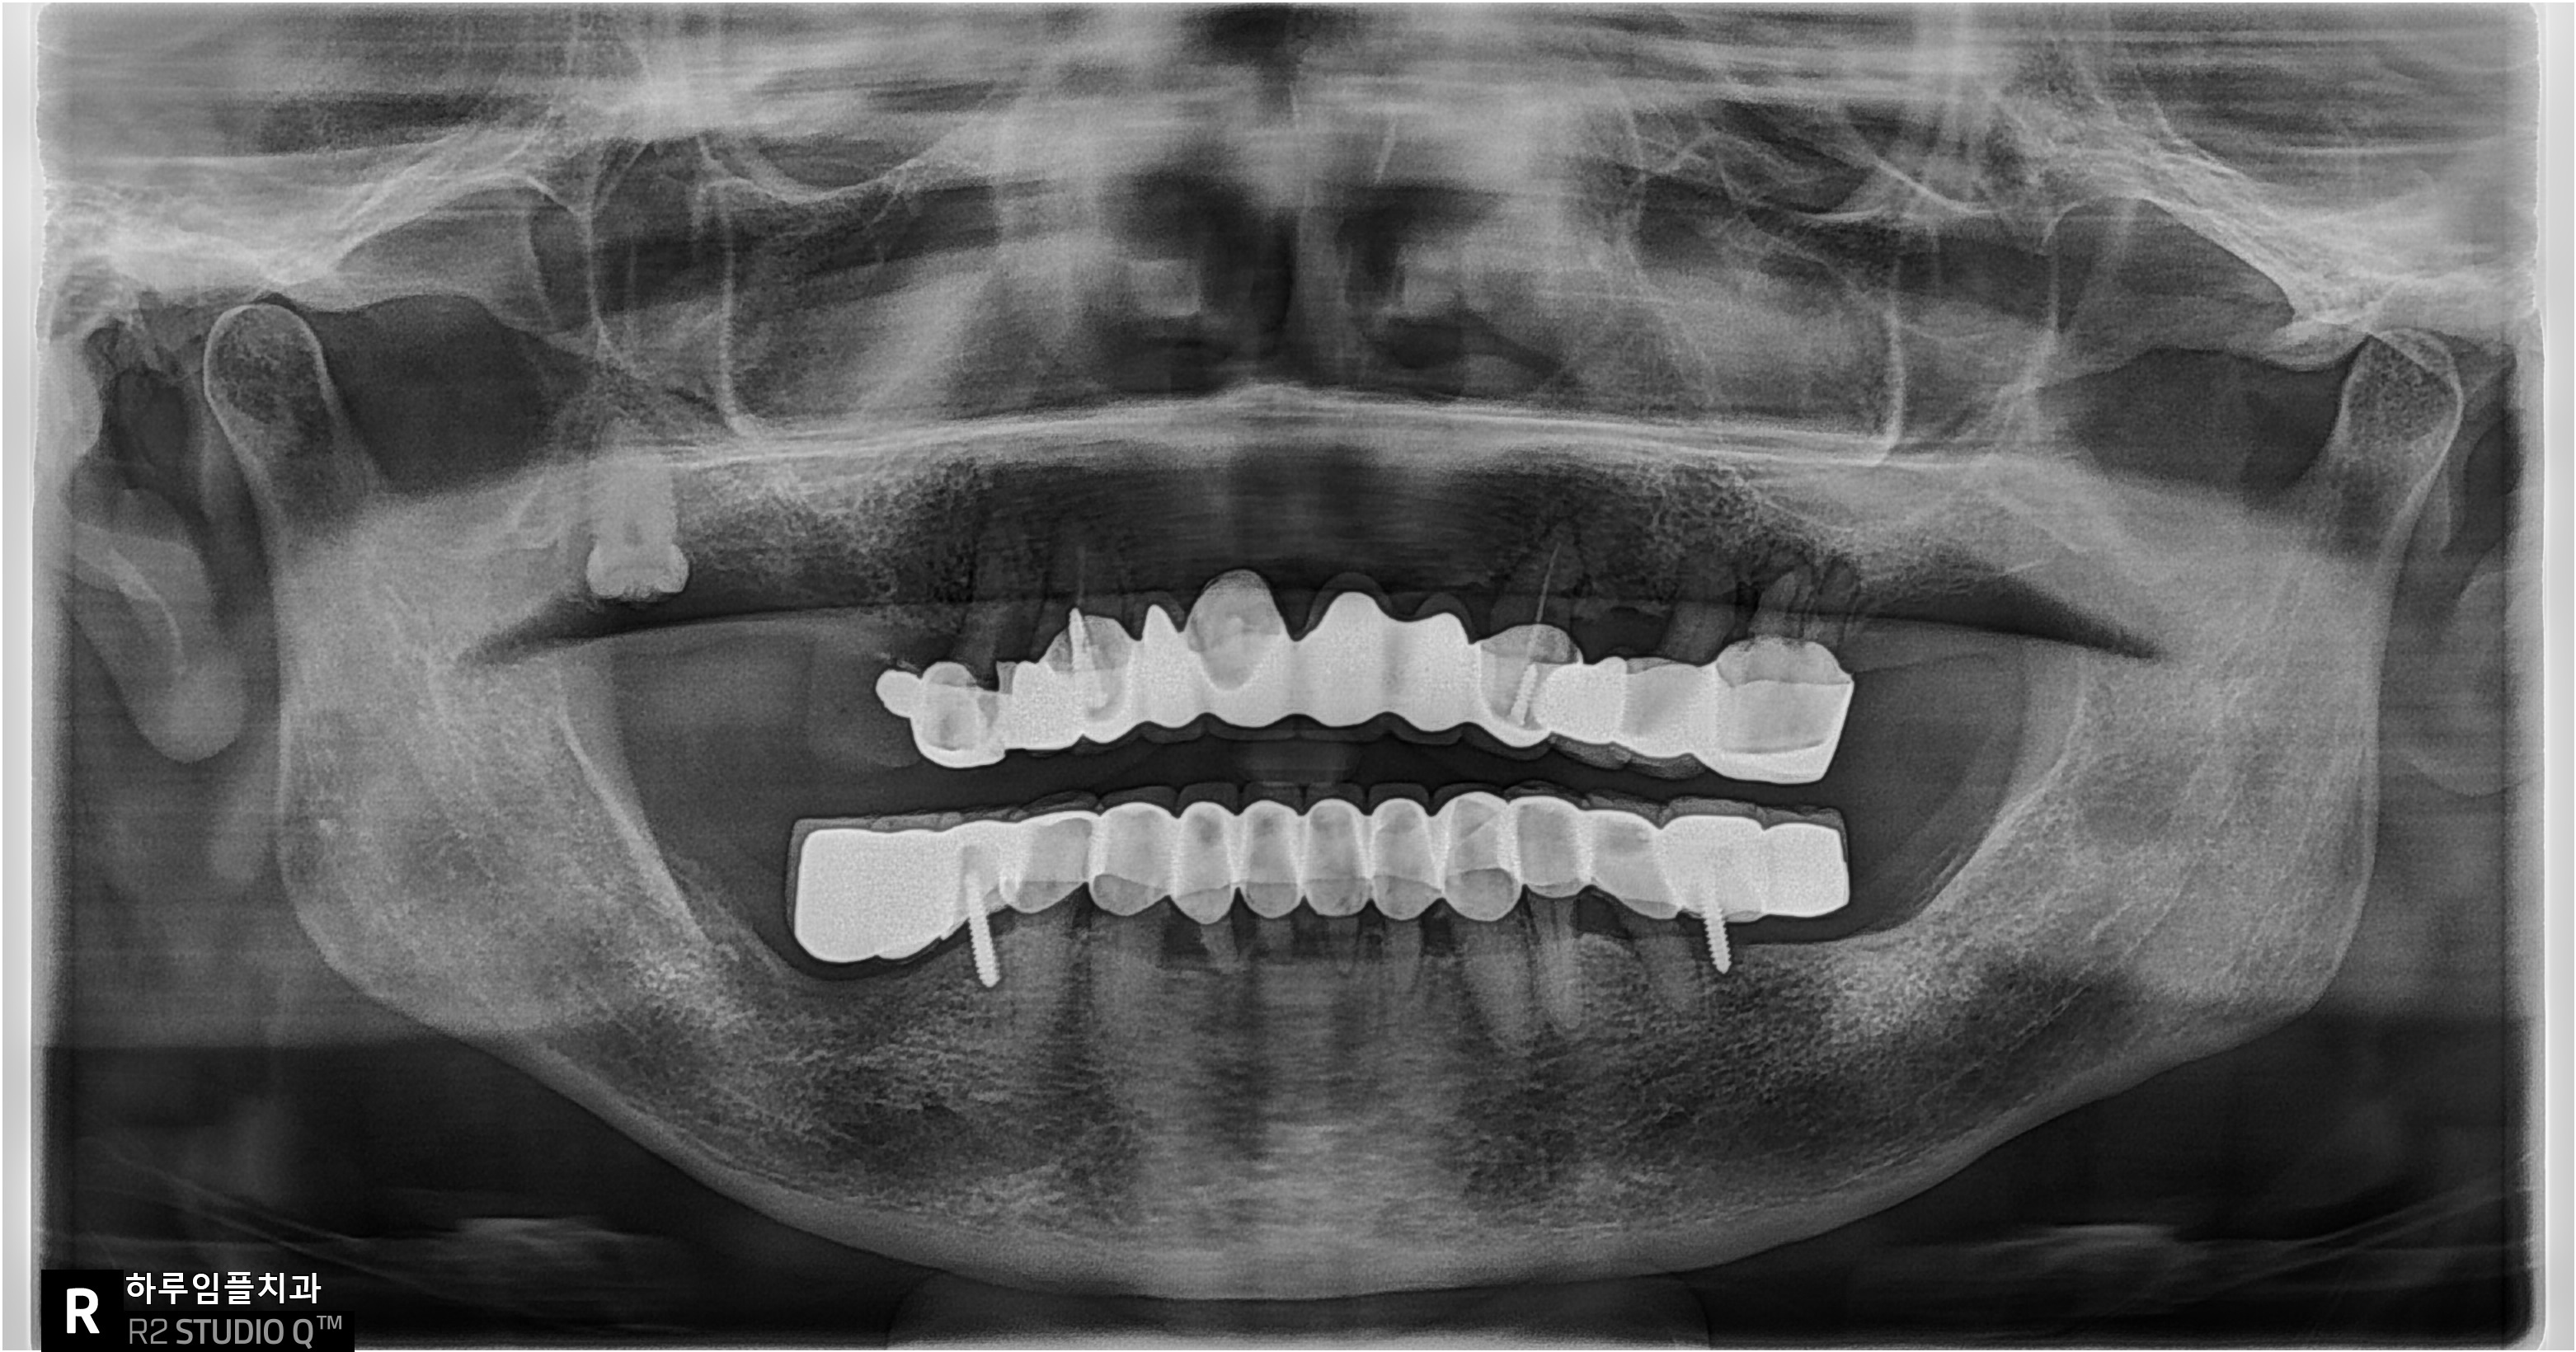

인공치근은

잇몸뼈와 완전히 붙기까지

평균 3~5개월 정도가 필요합니다.

그동안 임시보철로 생활하시다가,

잇몸이 안정되면

최종보철로 교체하게 됩니다.